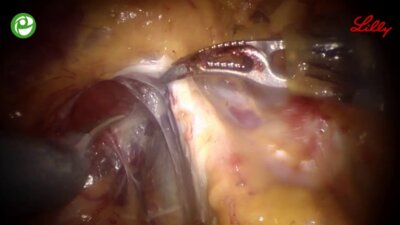

Операции на простате